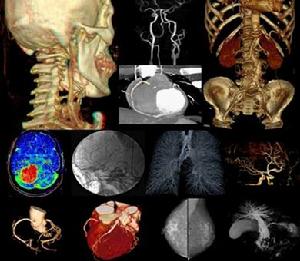

iMAGES引擎套用系統支持全DICOM的醫學影像數據,具有全功能的2D圖像處理,以及根據CR、DR、DSA以及乳腺的設備特點提供盈谷獨有的和弦圖像處理算法;對於多排CT,高場MR等先進影像設備,iMAGES提供了CT、MR的體數據分析功能,線上實現MRP、VR容積重建等高級功能,為放射科和臨床科室提供高效快速的線上圖像處理及分析結果的即時終端顯示,並提供在心臟、肺、肝臟、乳腺等方面的專業功能分析軟體包,全面滿足放射科的專業套用。

前瞻的理念,帶來全新的套用,隨著醫學影像技術及套用的飛速發展,盈谷科技利用多年的技術儲備,全面轉向支持大數據量的高清容積重建;提供多模多維的圖像融合技術,將產生更有效的套用圖像,便於醫生診斷和提供治療方案,並將可視化影像技術套用延伸到臨床及手術科室